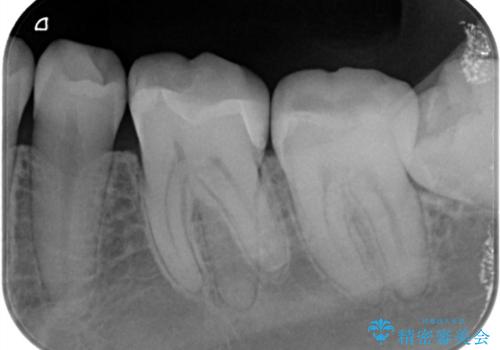

- 他院で虫歯と言われたが、銀歯は患者様自身嫌だということでインターネットで当院のサイトを見ていただき来院されました。

カウンセリングを進めていったところ、やはり銀歯は嫌だという話になりセラミックでの治療になりました。

銀歯の治療も悪いわけではありませんが、残念なことに再治療になることがよくあります。

再治療しないためにも、いい型取りの材料を使用し歯の形に適した被せ物にすることをお勧めいたします。